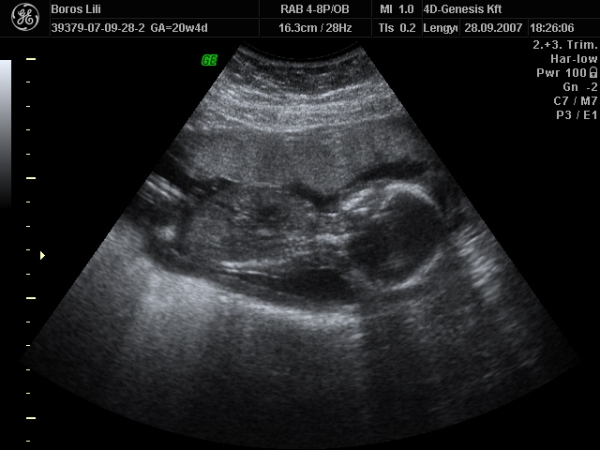

Szerintem nem vagy megőrülve! Ha hiszel ezekben a jelekben, tedd azt. Bár én az els terhességemnél abban voltam, hogy nekem fiam lesz. Aztán a 4d-n úgy széttette a kisasszony a lábait, hogy nem lehetett eltéveszteni. Nem volt egyáltalán rossz érzés, mert én is úgy voltam vele, hogy lényegtelen a neme, csak egészséges legyen.

Majd kb 5 hét múlva kiderül a 4d-s mozin.